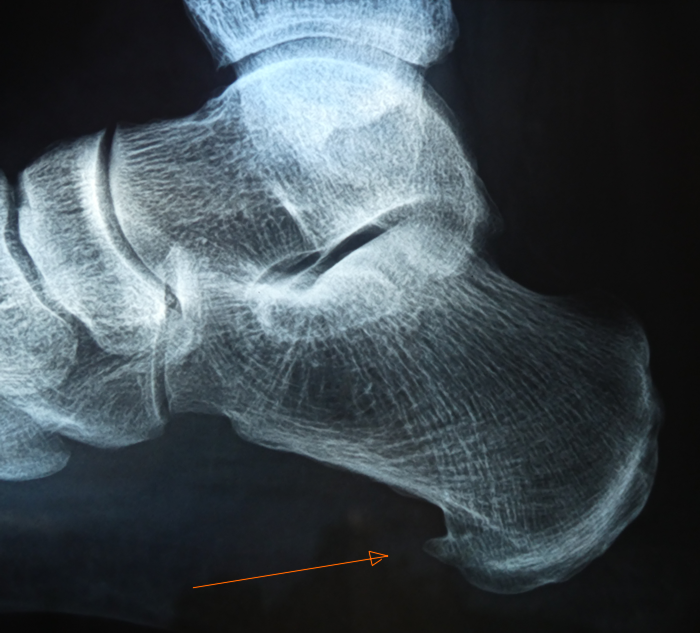

Fersensporn I | |

Der Fersensporn ist eine dornartige Kalkablagerung oder eine Verknöcherung der Sehne. |

Er bildet sich an der unteren oder oberen Ferse. |

Unterer Fersensporn |

Ursache oft längere Überbelastung des Fußgewölbes. |